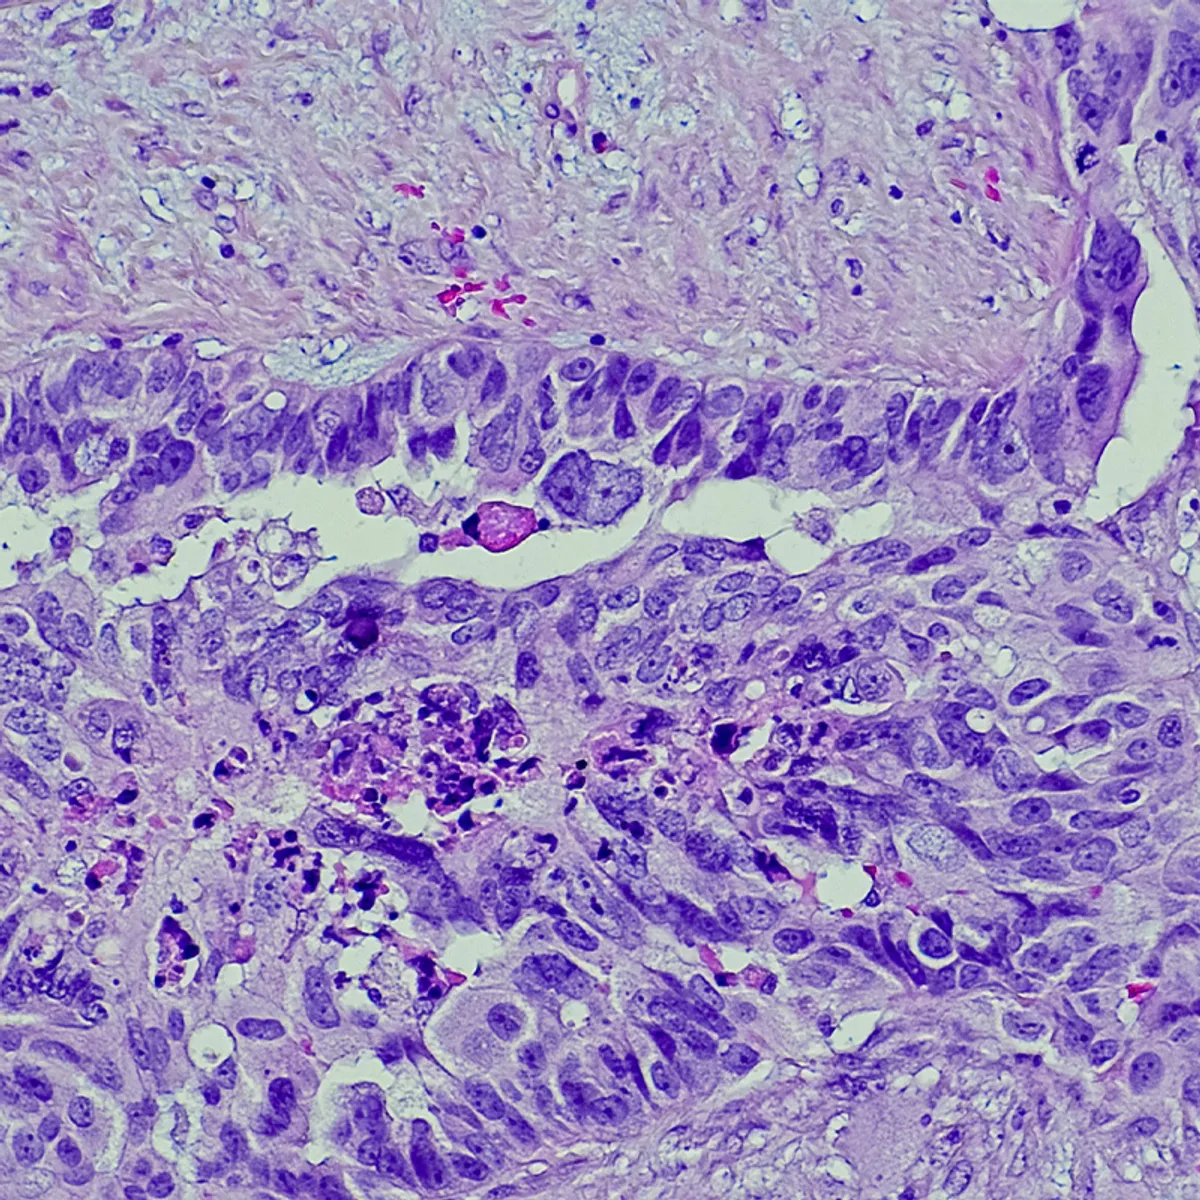

Treatment of recurrent endometrial cancer with metformin, letrozole, and abemaciclib

A combination, triplet therapy that targets cancer cells from within and without caused tumors to shrink or stabilize in nearly all patients with recurrent or persistent estrogen receptor- (ER-) positive endometrial cancer…

Kristen Foreman had an apple-sized mass near her left ovary, which was ovarian cancer. Doctors later discovered she had endometrial cancer, too.